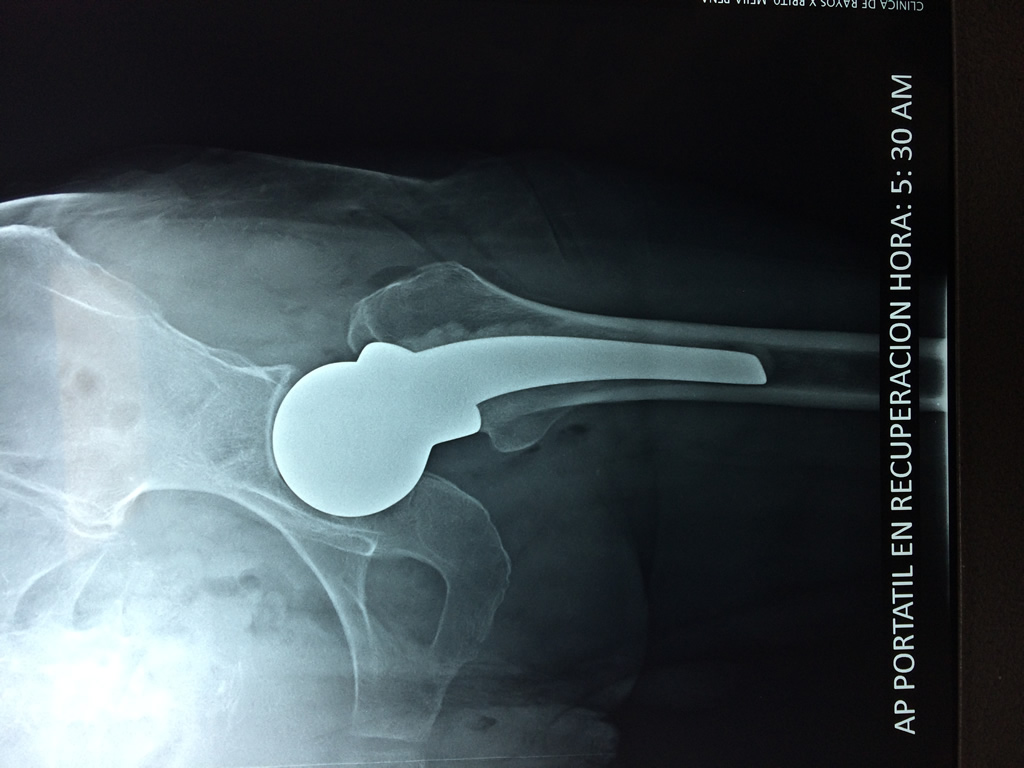

La cirugía de fractura de cadera se realiza para reparar una ruptura en la parte superior del hueso del muslo. Este hueso se denomina fémur.

Es parte de la articulación coxofemoral. Si una fractura de cadera no recibe tratamiento, es posible que deba permanecer en una silla o en la cama.

A menudo se recomienda la cirugía para reparar la fractura debido a dichos riesgos.